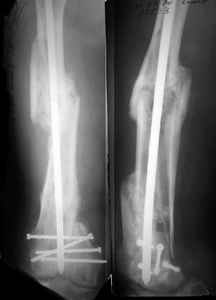

I presented a series of ~25 such cases at EuroTrauma'2004. Many cases were discussed here. I attach am example. Look also recent cases at http://www.hwbf.org/hwb/conf/alex58/scfx.htm,

http://www.hwbf.org/hwb/conf/alex63/alex63.htm